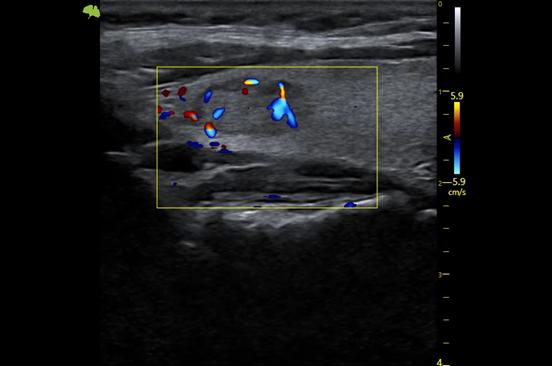

3. Công nghệ Doppler màu VFlow tiên tiến với độ nhạy cao hơn có thể giúp phát hiện ngay cả các mạch máu ngoại vi. Điều này cho phép chẩn đoán chính xác khi việc kiểm tra lưu lượng máu đặc biệt khó khăn.